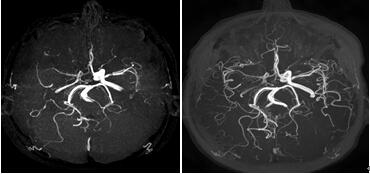

传统模拟磁共振颅脑MRA全数字磁共振颅脑MRA,清晰显示细小血管

1、更清晰:采用信号采集源头数字化+信号处理线圈接口数字化+信号传输全程数字化技术,实现了高清成像。